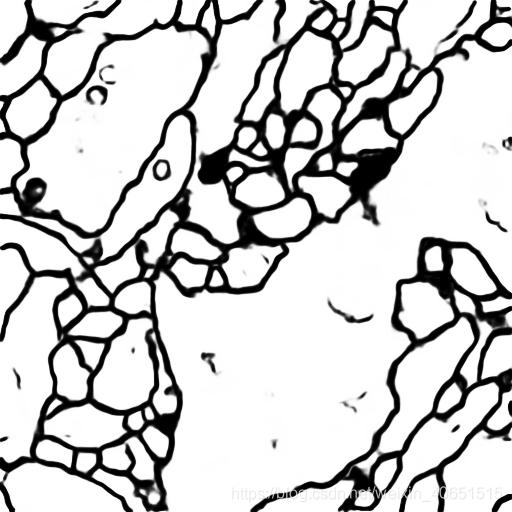

从图中我们发现 U-Net模型在经过简化之后,其在细胞分割任务中已经达到了不错的训练效果结果,其准确率高达78%,为了进一步提高模型准确率,我们需要在模型设计环节设计完整的 U-Net模型,并加大模型的训练次数,这样就能使模型很轻松的达到95%左右。

模型输出图像: